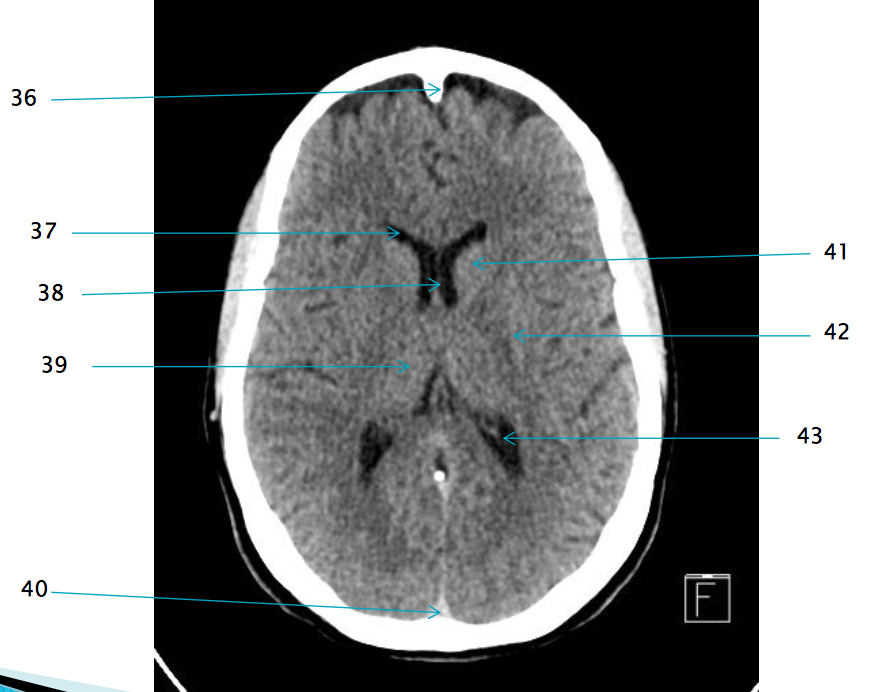

37

Frontal horn of R lateral ventricle

38

Septum pellucidum